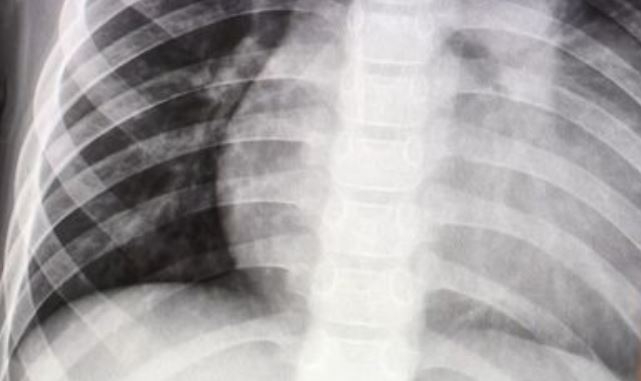

[헤럴드경제=김주리 기자] 일본 정부가 엑스레이(X-ray) 촬영에 의한 폐·유방·위암 판독에 인공지능(AI)을 활용하는 방안을 검토한다고 아사히신문이 24일 보도했다.

이날 연합뉴스 등에 따르면 후생노동성은 현재 폐암 등 검진 때 엑스레이 촬영 결과를 2명 이상의 의사가 판독하도록 권고하고 있다.

그러나 영상이나 사진에서 이상 여부를 찾아내는 AI 기술이 크게 발전함에 따라 AI를 활용해 검진 비용을 낮추기 위해 1차 판독을 AI에 맡겨도 검진 정확성이 유지될 수 있는지 검증하기로 했다.